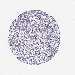

LYMPHOMA - Protein expressioni

A mouse-over function shows sample information and annotation data. Click on an image to view it in a full screen mode. Samples can be filtered based on level of antibody staining by selecting one or several of the following categories: high, medium, low and not detected. The assay and annotation is described here.

Each image is clickable and will lead to virtual microscopy that enables deeper exploration of all samples and also displays staining intensity scores, fraction scores and subcellular localization as well as patient and tissue information for each sample.

Antibody HPA036494

Staining

High

Medium

Low

Not detected

Intensity

Strong

Moderate

Weak

Negative

Quantity

>75%

75%-25%

<25%

None

Location

Nuclear

Cytoplasmic/membranous

Cytoplasmic/membranous,nuclear

Malignant lymphoma, non-Hodgkin's type, Low grade

Malignant lymphoma, non-Hodgkin's type, High grade

Hodgkin's disease, NOS

Hodgkin's lymphoma, nodular sclerosis